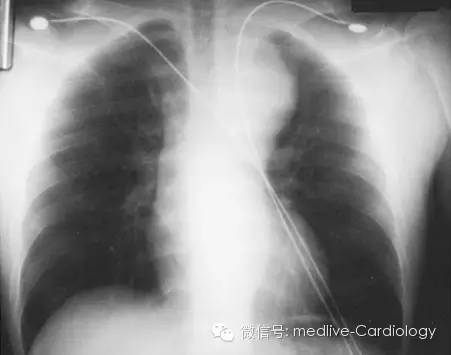

在诊断主动脉夹层的过程中,胸片常作为第一项影像学检查,虽然它敏感性和特异性均不高。如下图所示,纵膈影增宽是最常见的表现,特别是在升主动脉夹层的患者中更为常见。其它的表现包括双重主动脉结、主动脉壁钙化影内移、气管右移、心包积液、心影增大、左肺尖模糊、主动脉轮廓不规则、胸腔积液。